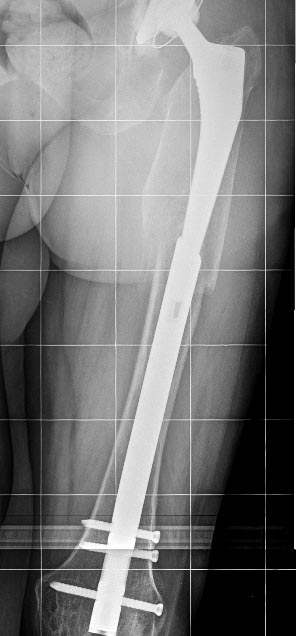

[Ortho] Перипротезный перелом

Искусно сделанная сложная операция, молодцы. Но можно было сделать иначе

- закрыто, быстро и надежно...

Имя     : Bedrennaya Lat.jpg